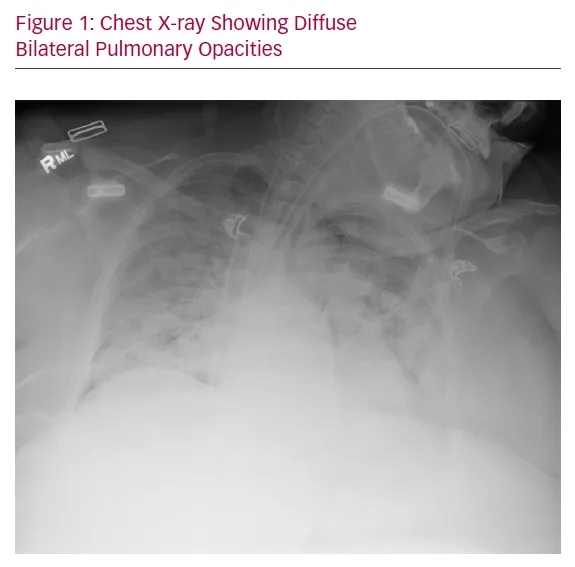

ARDS: Sepsis-induced hypoxemia ($PaO₂/FiO₂ \le 300$) with bilateral infiltrates on CXR. A major cause of mortality.